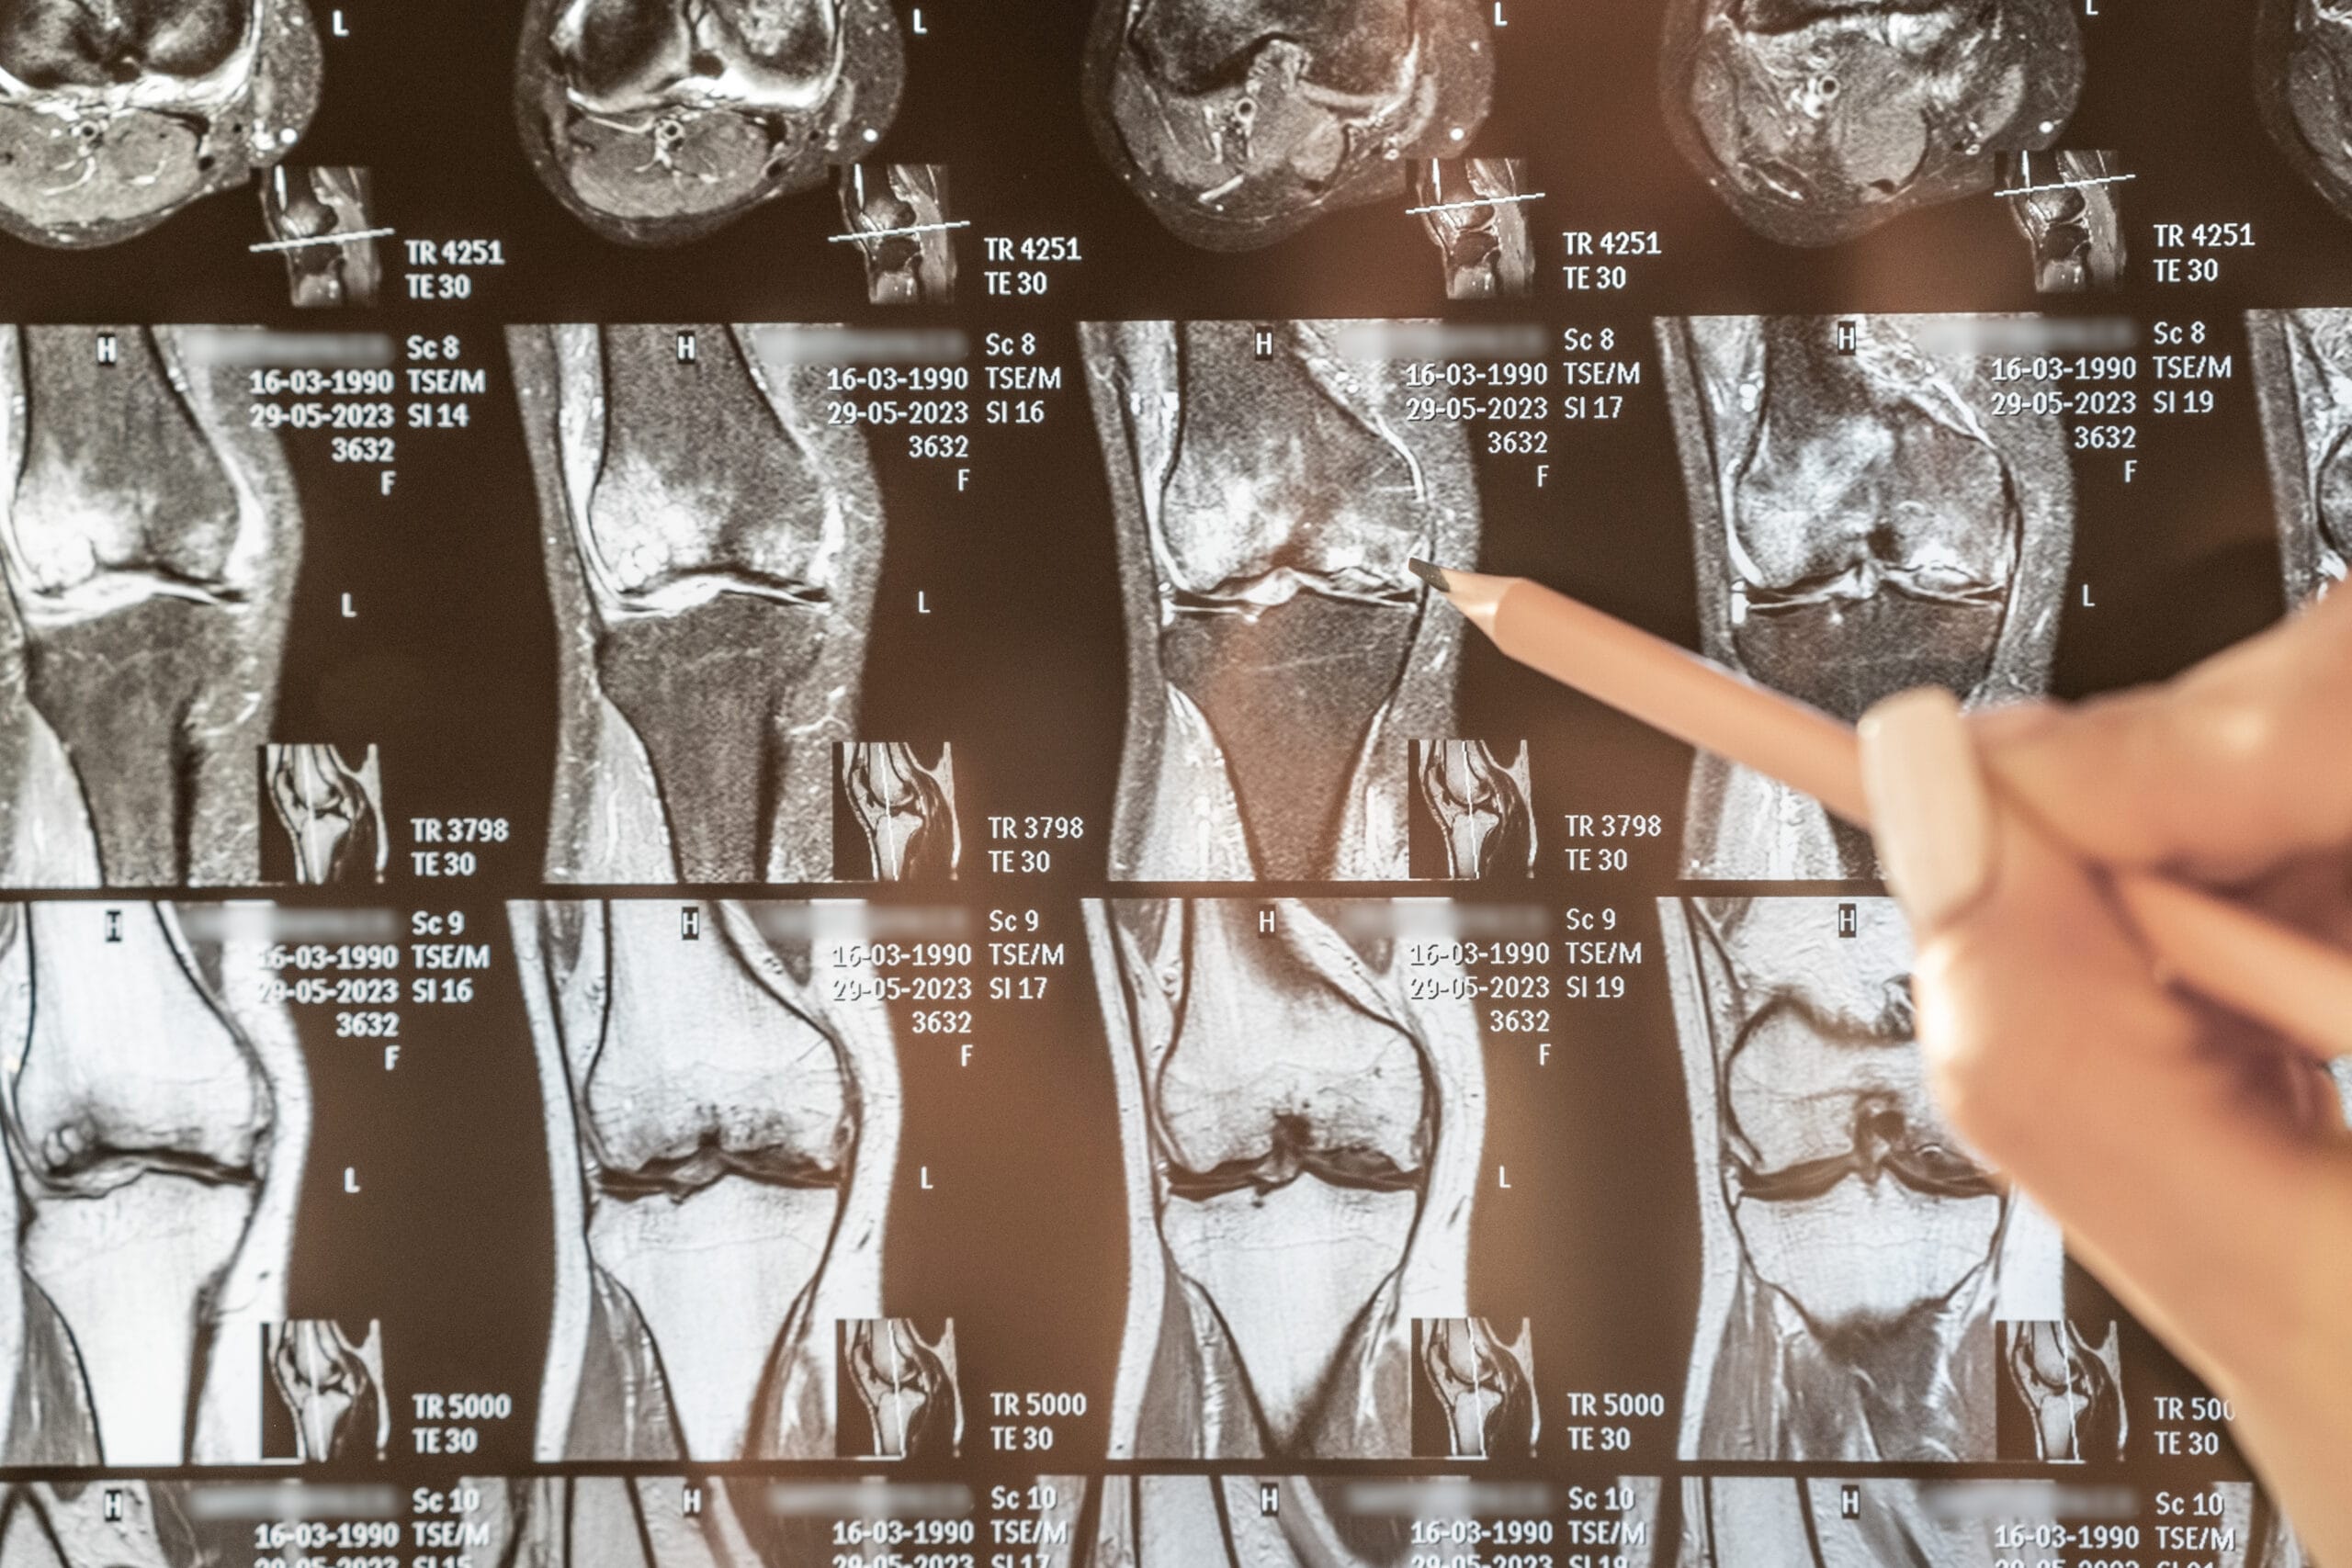

Người cao tuổi có thể gặp tình trạng đau nhức ở bất cứ khớp nào trên cơ thể. Theo thống kê cho thấy những vị trí khớp thường bị đau nhức ở người lớn tuổi là:

Có khoảng 30.6% người bệnh đau nhức đầu gối và tỷ lệ tăng dần theo độ tuổi ở nữ giới.

1. Viêm xương khớp/thoái hóa khớp

Tuổi càng cao thì lớp đệm tự nhiên nằm giữa sụn khớp sẽ bị suy giảm khiến sụn bị mỏng, mòn, yếu, dễ bị tổn thương.

Khi lớp sụn này biến mất, 2 đầu của xương sẽ cọ xát với nhau gây ra sưng, đau, không còn linh hoạt, có thể xuất hiện gai xương.

Hiện tượng thoái hóa khớp thường diễn ra ở người có độ tuổi từ 40 – 60 và là 1 căn bệnh mạn tính.